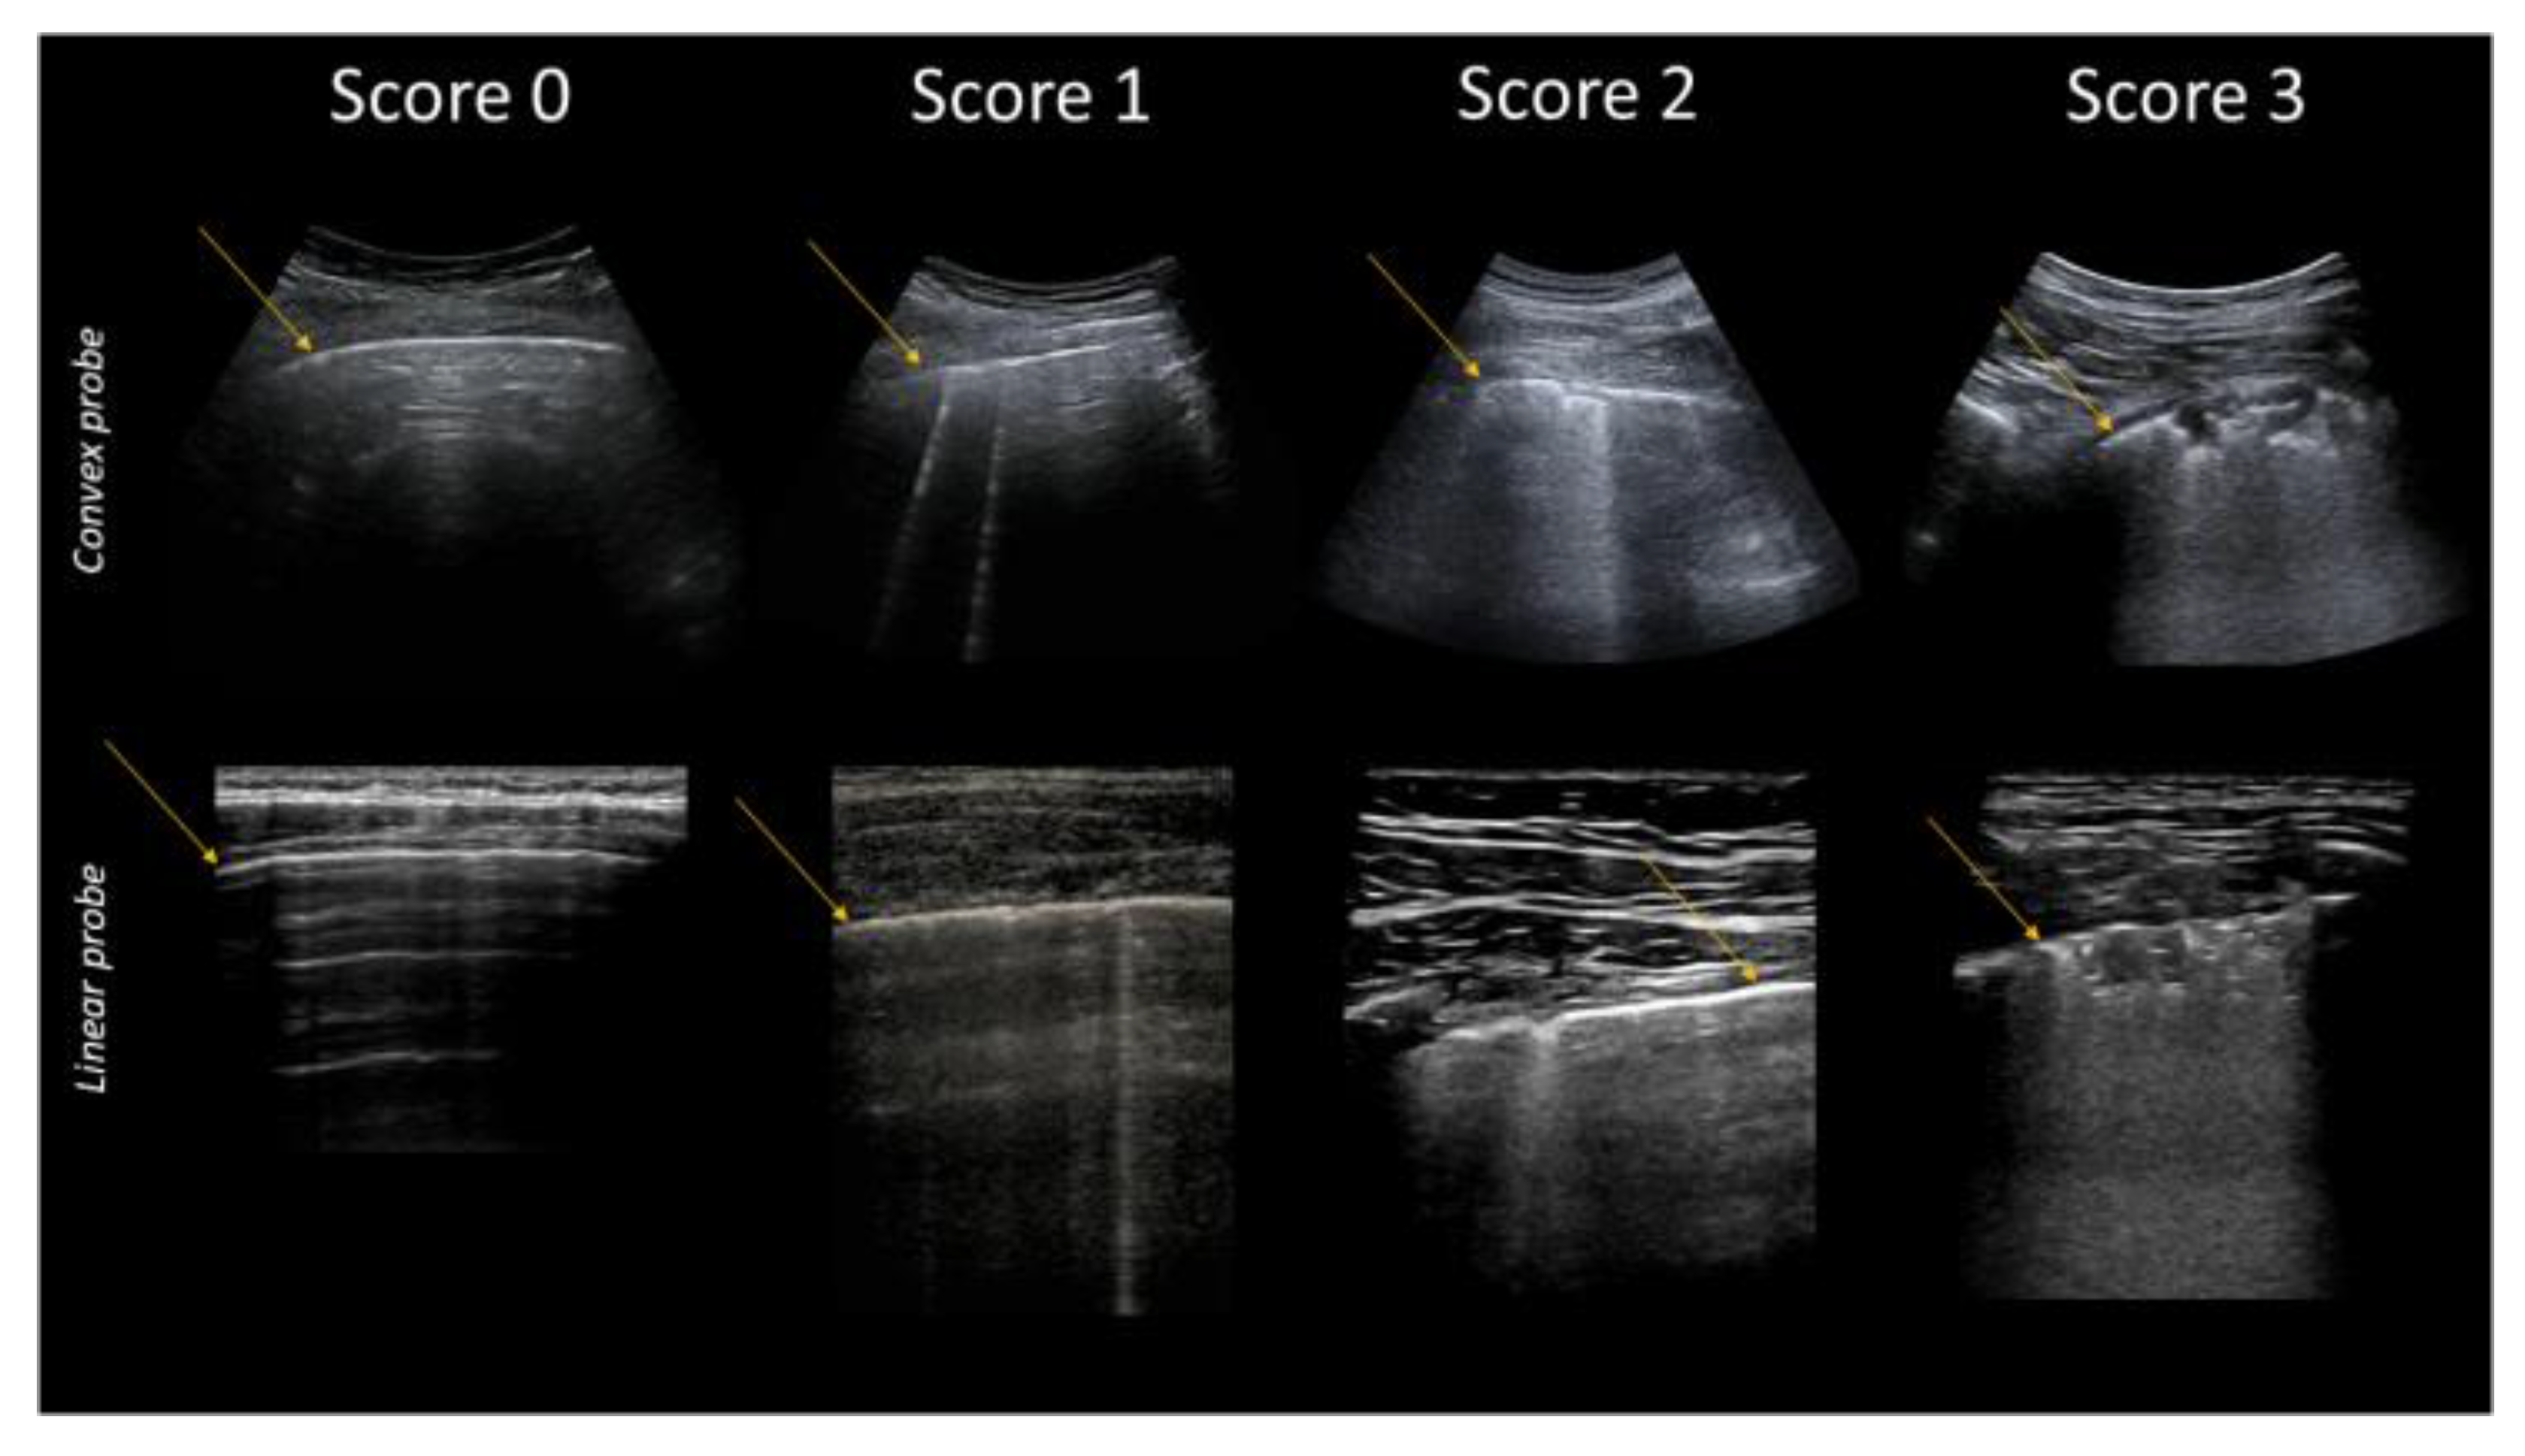

| Score | Description |

|---|---|

| 0 | Pleural line is regular. Horizontal artifacts and mirror effects are present. Normal lung. |

| 1 | Pleural line has slight alterations with sporadic vertical bright artifacts. The presence of relatively small acoustic channels due to focal interstitial thickening is speculated. |

| 2 | Pleural line has relevant alterations. Progression of subversion of peripheral air space geometry causes a predominance of vertical artifacts. Small subpleural consolidations, related to deaeration, can be present. |

| 3 | Pleural line is irregular and cobbled. Subpleural lung is denser and more disordered. White lung with or without larger consolidations may be present. Small and large consolidations are subpleural regions minimally or completely deprived of air. |